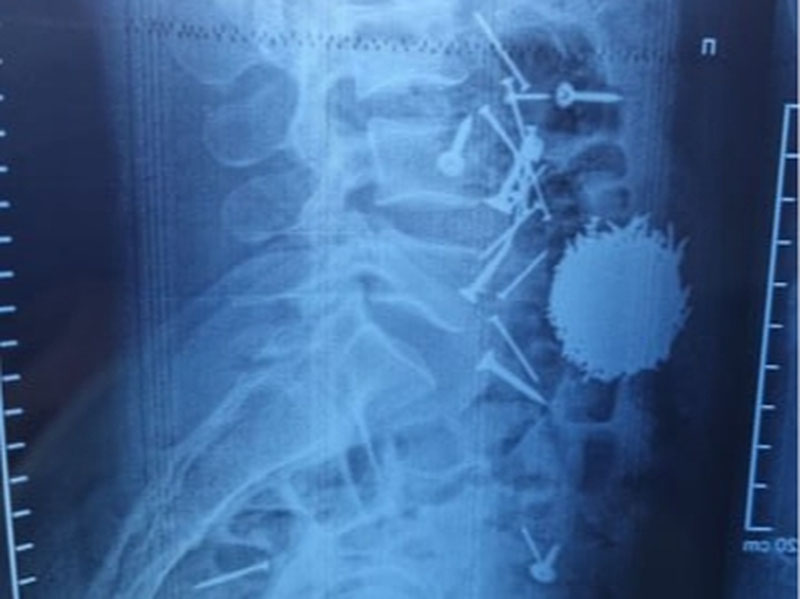

Отмечается, что 29-летний гражданин А. Е. был доставлен в медицинское учреждение с жалобами на сильные боли в области живота. По результатам диагностики и лабораторных исследований, проведённых в приёмном отделении, в желудочно-кишечном тракте пациента было выявлено большое количество инородных тел — гвоздей и саморезов.

Пациенту в экстренном порядке была проведена хирургическая операция методом лапаротомии и гастростомии, в ходе которой из брюшной полости были извлечены гвозди и другие металлические предметы. В настоящее время состояние пациента оценивается как удовлетворительное.